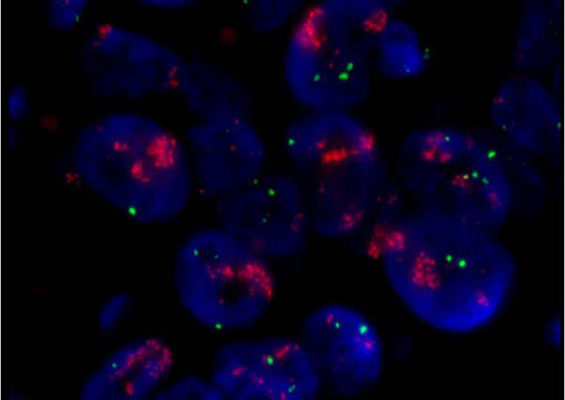

A laboratory test that can be used to look for HER-2/neu gene amplification in breast cancers. This test uses a probe molecule that has an attached fluorescent tag; when the HER-2/neu gene is present, the probe binds to the gene and shines brightly. The number of genes can be counted using a special fluorescent light microscope.

A type of DNA mutation in which a single gene is duplicated multiple times to increase its activity.